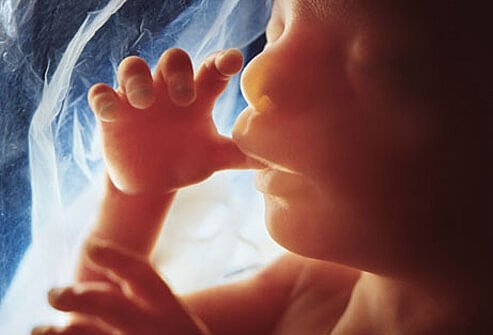

• Third Month

Third Month

By now the fetus is 1 inch long and is fully formed. He/she has begun swallowing and kicking. All organs and muscles have formed and are beginning to function.